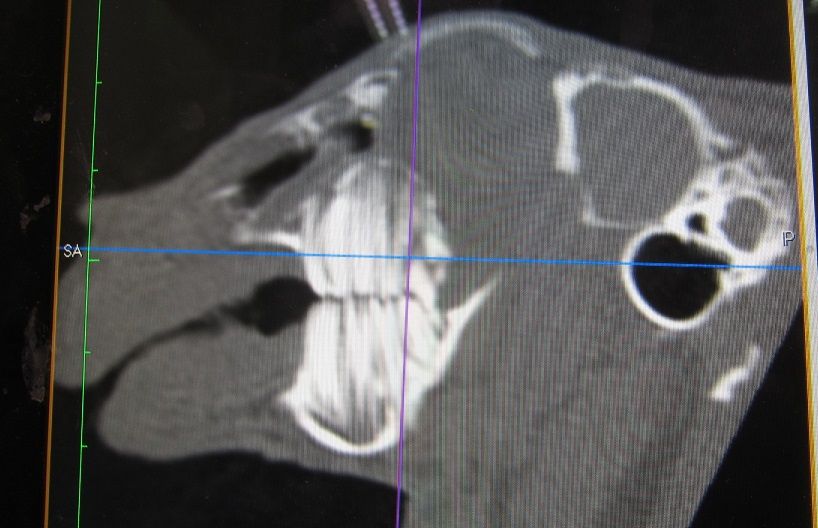

途中経過をCTで

まだまだたくさん残ってますが、👆これが👇こうなります。

完全に取り切れてない部分もありますが、すでに時間もかなりかかっていたのでひとまず終了。